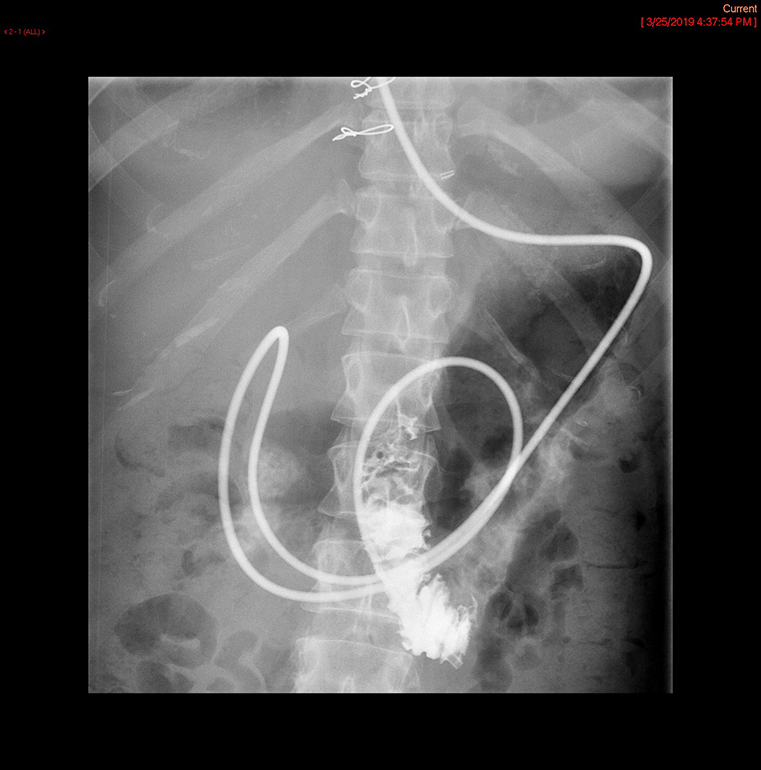

- The technologist will obtain a scout radiograph to include the upper abdomen. Evaluate for the location of the surgical chain sutures

(key image 1).

- There are usually two "sets" of surgical chain sutures.

- The first is located in the epigastric area at the level of the gastrojejunal anastomosis.

- The second is usually located in the left midabdomen. This is the site of the jejunojejunal anastomosis.